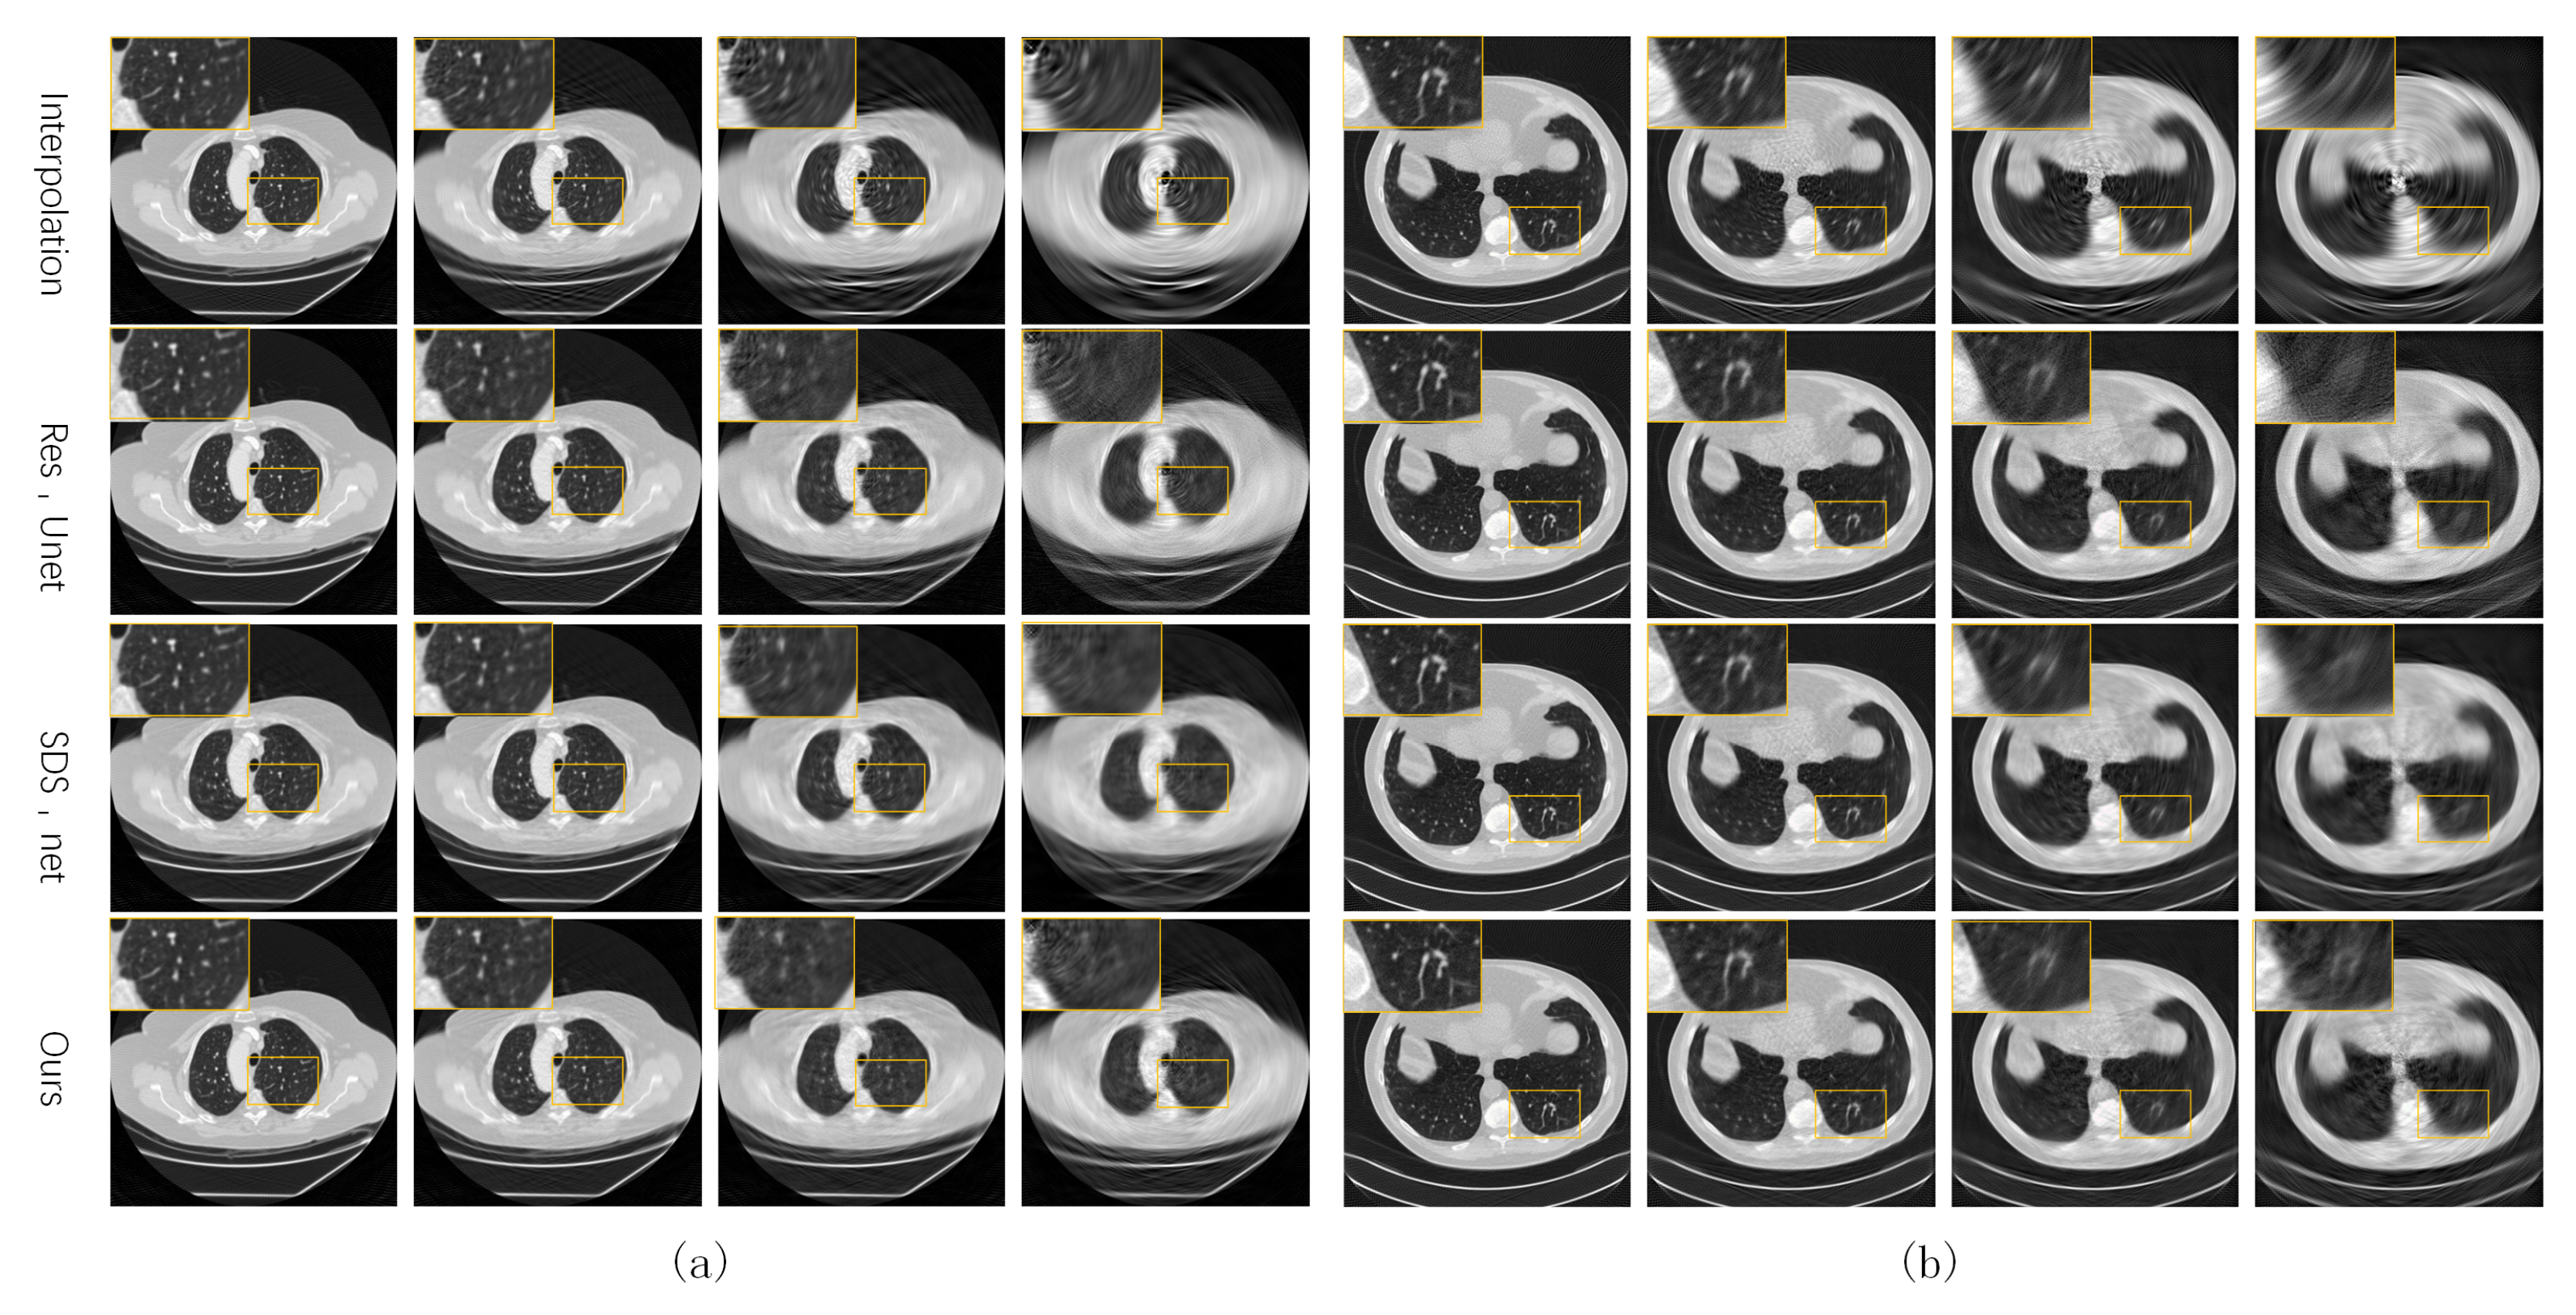

Figure 4 shows some test CT slices reconstructed by the four methods on the two datasets. The reconstructed images of the three machine-learning-based models are close and significantly better than those of linear interpolation. As the sparsity level s increases, the quality of all reconstructed CT images decreases significantly, and the linear interpolation method degrades the most significantly due to not using prior knowledge in the training set. Our network performs slightly better than the two baseline networks (SDS-net and Res-Unet) at higher sparse levels (). As shown in the local zooms corresponding to and 15, the proposed network is better in terms of edge preservation of CT images.

Figure 4.

Reconstructed CT images of the four methods from our own dataset (a) and the AAPM dataset (b).